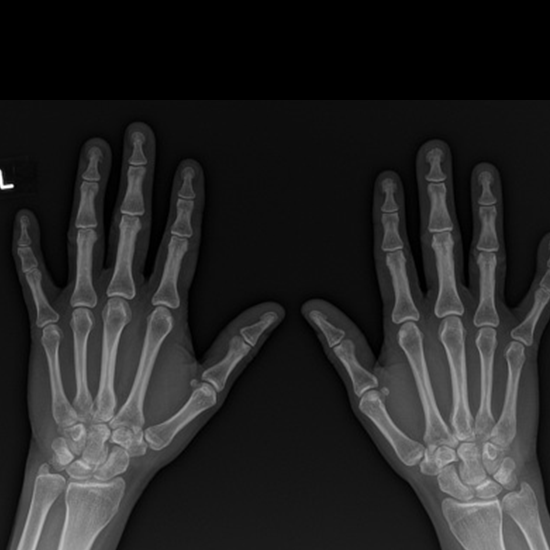

X-ray Both Hand AP View

Both Hands X-Rayed AP View uses a small amount of radiation to help see the hands and the area around them. The bones in the wrist are called carpal bones. The bones between the carpal bones and the fingers are called metacarpal bones (phalanges).